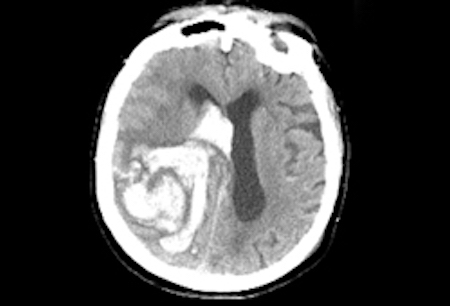

- tomografía computarizada (TC) de cabeza sin contraste.